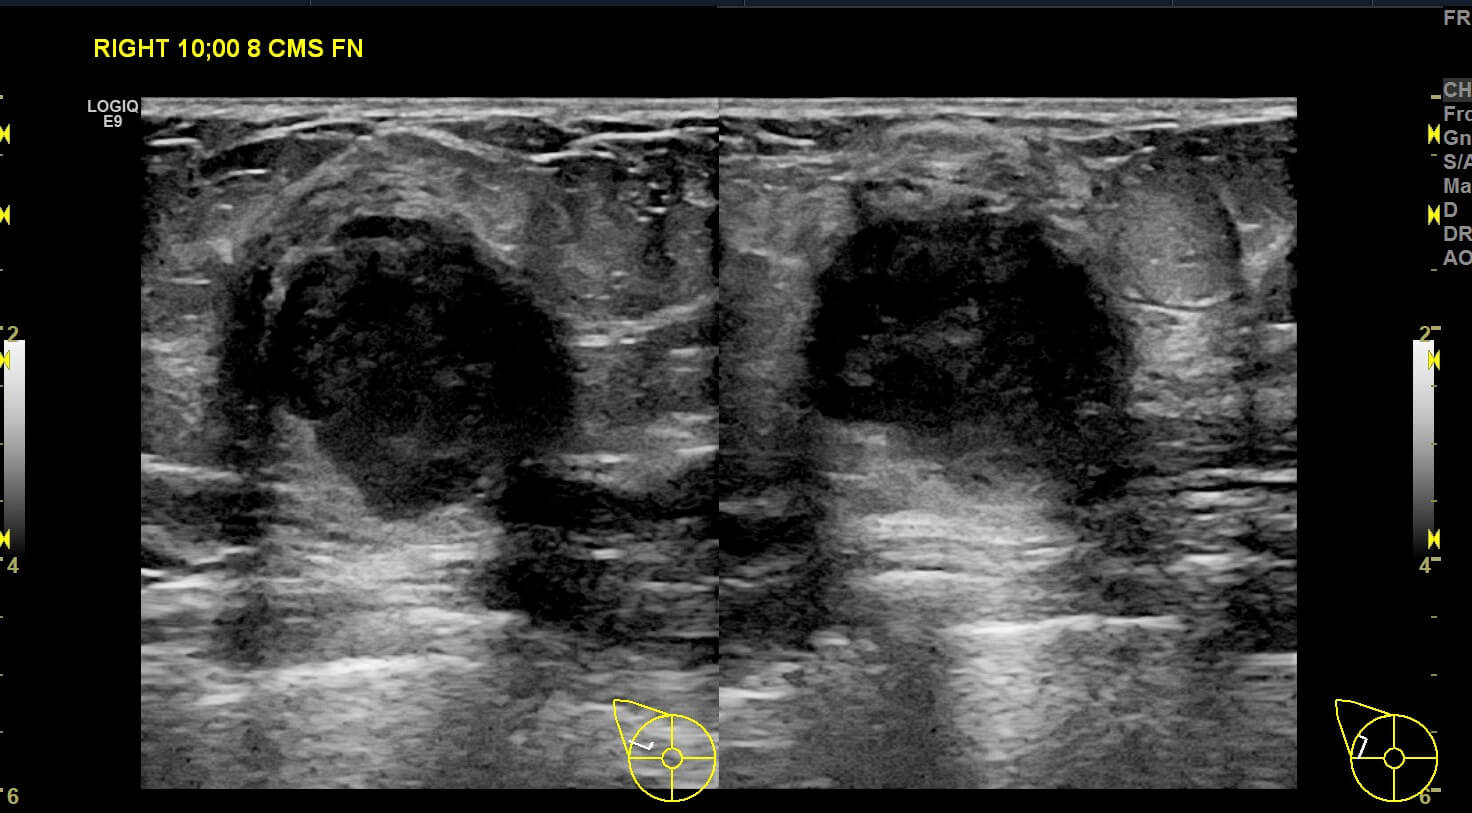

Mammogram revealed the presence of an irregular high density mass in the posterior third of the upper outer quadrant of the right breast with indistinct margins on two-dimensional mammogram. No internal calcification seen. No overlying skin thickening or retraction noted. DBT (Digital breast tomosynthesis) revealed the mass having spiculated margins and irregular shape. Corroborative ultrasound showed an irregular, heteroechoic solid mass at 10-11 O’clock position with anti-parallel orientation, microlobulated margins, posterior enhancement and internal necrotic/ cystic areas within. Mild internal vascularity was seen on color Doppler. No dilated ducts or intraductal extension was seen. No suspicious lymph nodes were present Further recommendation: Ultrasound guided core-needle biopsy with immunohistochemical analysis Management received: Right side lumpectomy with MRM Final histopathology: Metaplastic carcinoma (carcinosarcoma) with no nodal metastasis